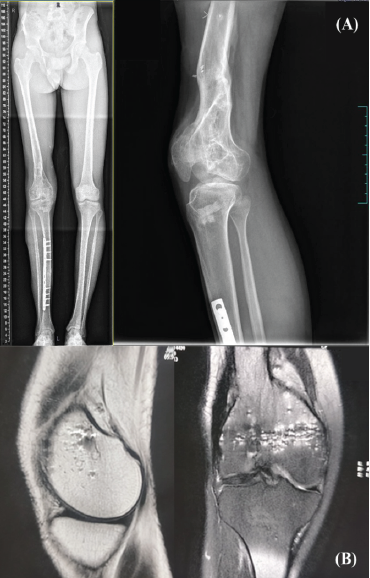

Long leg and lateral radiographs confirmed bony ankylosis of the patella (Fig. 1).

Figure 1: (a) Pre-operative long leg and lateral radiographs depicting deformed distal femur with ankylosed patellofemoral joint, (b) Pre-operative magnetic resonance imaging image of the right knee, showing only minimal cartilage thinning in the medial compartment.

The patient exhibited joint space narrowing in the medial compartment of the knee on radiographs; however, on magnetic resonance imaging (MRI), there was only minimal cartilage thinning (Fig. 1). Notably, a skyline patella view radiograph could not be obtained due to the existing deformity. We ruled out the possibility of infections since the total count and inflammatory markers were within the normal range, and the MRI showed no signs of infection. Given the distorted anatomy, RA-PFA using the MAKO Robot (Stryker, USA), complemented by a quadriceps-plasty procedure, was planned. 3D-CT scan was performed to facilitate precise pre-operative planning. A MAKO product specialist segmented the scans using the MAKO planning software. Since the patella was ankylosed, the patella and femur were taken en bloc for segmentation, unlike regular cases (Fig. 2).